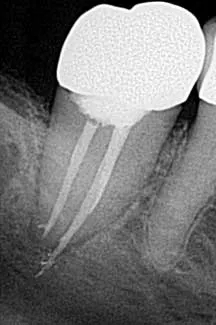

• Underfilling/overfilling

Underfilling of a canal can be caused by blockage, inadequate cleaning and shaping, ledging, and insufficient condensation pressure (figure 4). (1) Prevention is assessment via radiographs with removal and retreatment. Failure of the root canal can ensue, leading to the need for surgery or extraction.